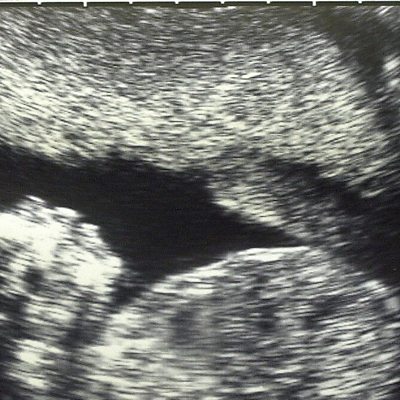

Mercy and Kirsteen share a very special moment with Laura, hearing her baby's heartbeat for the first time and discuss what it was like for them.